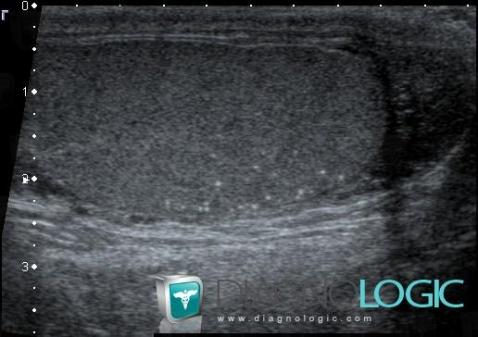

Testicular microlithiasis, Scrotum, US

Here is the specific information in the key image above:

- Diagnosis Testicular microlithiasis, Location(s) Scrotum, with gamuts Testicular calcification